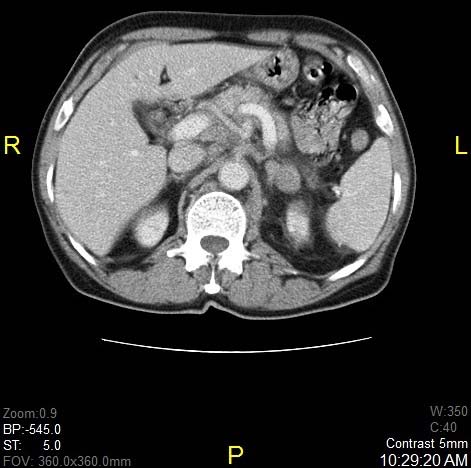

CT scan of thorax and abdomen revealed bilateral pretracheal, paratracheal, aortopulmonary, precarinal and subcarinal lymph nodes, largest measuring 4.6 x 2.9 cm [Table/Fig-1]. Lung nodules suspicious of metastasis was seen. Nodules in left adrenal gland and, necrotic abdominal nodes were also seen [Table/Fig-2]. FDG –F 18 PET/CT scan was performed and it confirmed metabolically active lesion in above sites. Differential diagnosis of lymphoma was also considered.

Axial post contrast CT of upper abdomen showing metastasis in left adrenal gland, multiple paraaortic, and retrocaval and peripancreatic lymph nodes.